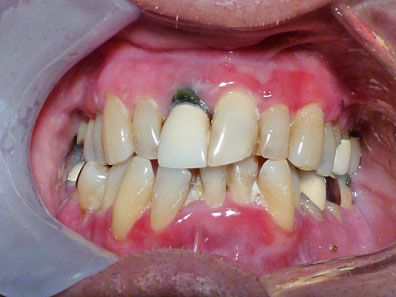

Figure 4

– The condition of the patient’s gingiva improved after treatment.

Intervention

The patient’s primary care physician prescribed prednisolone acetate 1% eye drops (1 drop in each eye 4 times a day) and a trial of high-dose prednisone (six 5-mg tablets initially for 3 days decreasing every 3 days by 1 tablet). His oral medicine specialist prescribed fluocinonide gel 0.05% (Disp 300 mL; rinse mouth with 1 teaspoonful for 3 minutes twice a day for a month) for long-term management of the oral lesions. The patient’s condition improved significantly over several months with this therapeutic strategy (Figure 4). Improvement was maintained with use of fluocinonide gel on an as-needed basis.